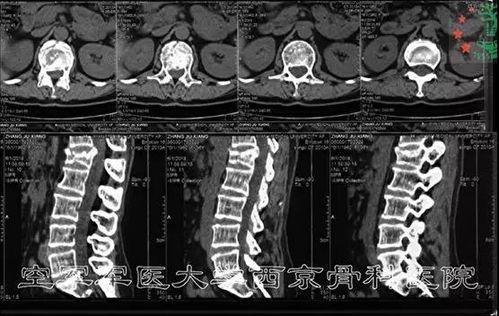

腰椎手术有很多种类型,比如椎间盘摘除术、椎管减压术、椎体融合术等。每种手术都有其独特的适应症和手术方法。下面,我们就来了解一下几种常见的腰椎手术。

2. 椎管减压术:当腰椎管狭窄导致神经受压时,医生会进行椎管减压术。这种手术通过扩大椎管,减轻神经压迫,缓解症状。

3. 椎体融合术:对于腰椎不稳或椎体骨折的患者,医生会进行椎体融合术。通过将相邻的椎体连接起来,恢复脊柱的稳定性。